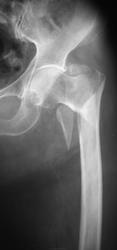

Чрезвертельный с отрывом малого вертела, смещением бедренной кости кверху и кнаружи.

И кажется не свежий

С переломом все ясно, согласна с коллегами. А структура головки по нижнему контуру не смущает?

Ну кажется, что это кистовидная перестройка, да ещё и обезыствление стенок артерии

Оскольчатый чрезвертельный со смещением и уменьшением шеечно-диафизарного угла. Боковой снимок?

Смущает. Асептический некроз головки?